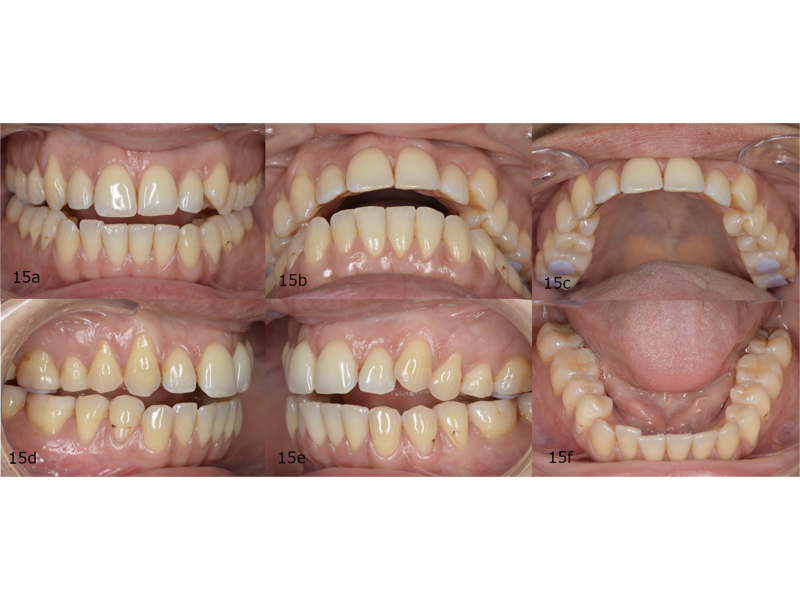

When measuring the size of her teeth and conducting a Bolton analysis, we identified an anterior Bolton discrepancy due to mandibular excess (Fig. 8). In maximum intercuspation, there were bilateral contacts only on the posterior teeth (Fig. 9). In her arc of closure (Fig. 10), a unilateral posterior fulcrum was observed. It was due to premature contact on the maxillary left second molars.

Figs. 9a–f: (a) Frontal view. (b) Overjet view. (c) Left lateral view. (d) Upper oclussal view. (e) Right lateral view. (f) Lower oclussal view.

After four months of wearing the splint, the patient’s condylar position was stable (Fig. 13). This position was maintained during treatment in order to retain the true arc of closure by placing occlusal build-ups on the posterior teeth (Figs. 14 & 15). These occlusal build-ups also have an intrusion effect, favouring the correction of patients who require vertical control. Only when the patient is stable do we have a predictable situation for planning and starting orthodontic treatment. In treatment with aligners, planning based on the patient’s true arc of closure allows us to achieve successful results in less treatment time and with fewer aligners and fewer refinements while protecting the TMJ.